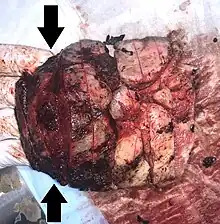

| Gross pathology of severe intervillositis, with dark red and soggy tissue. | |

Chronic Histiocytic Intervillositis (CHI or CHIV) also known as Chronic Intervillositis of Unknown (A)etiology (CIUE) and Massive Chronic Intervillositis (MCI) is defined as a diffuse infiltration of mononuclear cells (histiocytes, lymphocytes, monocytes) of maternal origin into the intervillous space within the placenta. It often results in severe intrauterine growth restriction which can lead to miscarriage or stillbirth. Overall perinatal mortality rate is high: 41%[6] to 77%.[7] Recurrence rate is also high: 67%[7] to 100%.[6]